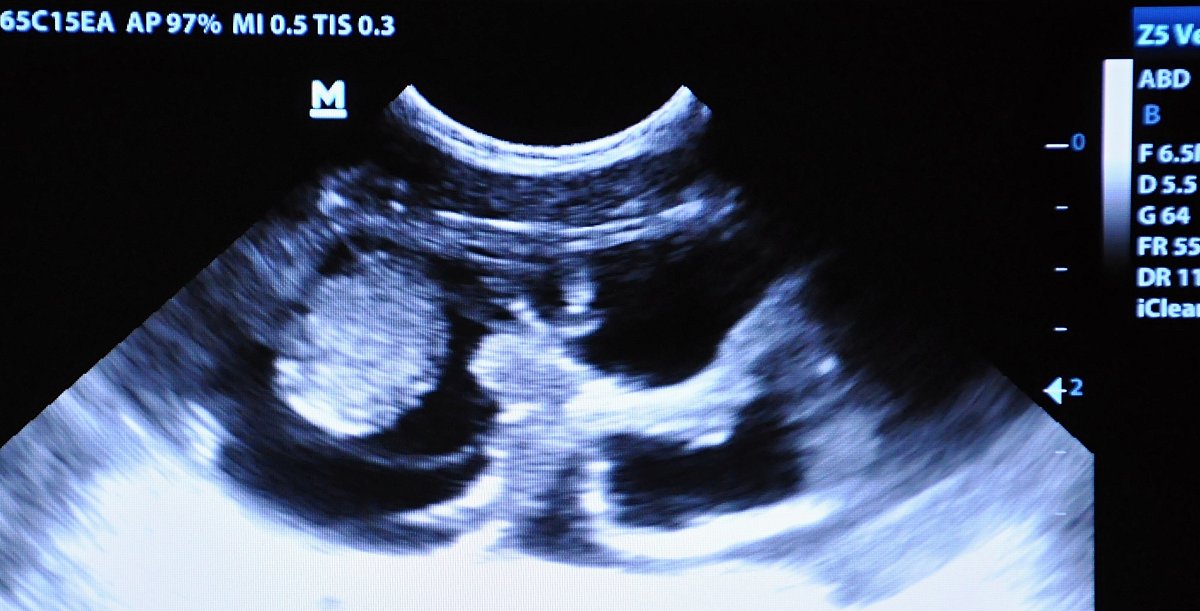

Ultrazvukové vyšetření potvrdilo březost luskouní samice. FOTO: Roman Vodička, Zoo Praha

Mimořádně náročný chov těchto choulostivých tvorů má na starost chovatel David Vala. „Náš pár luskounů jsme po povinné měsíční karanténě začali sbližovat přes kontaktní šubr, jakési seznamovací okénko, jelikož se zvířata neznala. Po měsíci jsme luskouny spojili a k našemu překvapení se ihned začali pářit. Výhodou je, že je od příjezdu trénujeme k vyšetření na speciální hrazdičce, které nám umožní provést ultrazvuk i odběr krve,“ popisuje Vala s tím, že první vyšetření v srpnu březost neodhalilo. To druhé už nenechalo prostor pro domněnky.